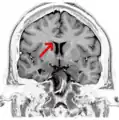

Corpus callosum from above, front part at the top of the image.